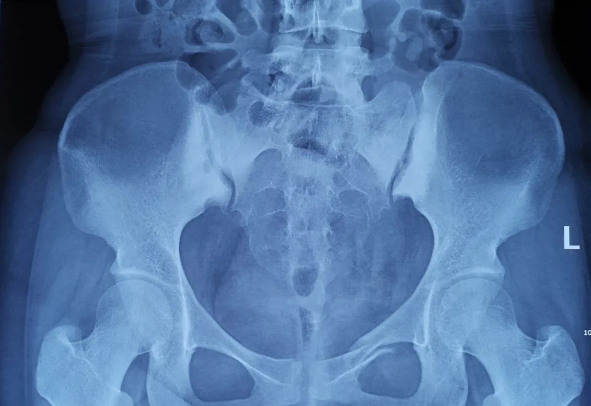

2025-02-28智匯天璣|高齡不是禁區(qū)!北京積水潭醫(yī)院智能骨科機(jī)器人助力90歲骨盆骨折患者重獲行走

由北京積水潭醫(yī)院院長蔣協(xié)遠(yuǎn)、智能骨科研究型病房主任王軍強(qiáng)帶領(lǐng)的智能骨科團(tuán)隊,運(yùn)用骨科機(jī)器人輔助經(jīng)皮骨盆通道螺釘置入技術(shù),成功救治了一名90歲高齡的骨盆骨折患者。 -

2021-01-06天璣骨科手術(shù)機(jī)器人落戶南昌市第一醫(yī)院,助力骨盆骨折閉合復(fù)位內(nèi)固定術(shù)順利完成

近日,天璣?骨科手術(shù)機(jī)器人落戶南昌市第一醫(yī)院,助力骨盆骨折閉合復(fù)位內(nèi)固定術(shù)順利完成。作為江西省首先采用5G引導(dǎo)下的骨科機(jī)器人手術(shù),天璣?骨科手術(shù)機(jī)器人用它的“透視眼”,以三維影像掃描進(jìn)行深層三維空間精準(zhǔn)定位,為患者“量身定做”了最理想、最安全的教科書般通道,完成了復(fù)雜骨盆骨折微創(chuàng)治療一次性完美置釘及腰椎骨折微創(chuàng)經(jīng)皮置釘?shù)氖仔悖蔀榻魇」强瓢l(fā)展的標(biāo)志性事件,同時也是江西省骨科步入新型數(shù)字智慧骨科時代的重要里程碑事件。 -